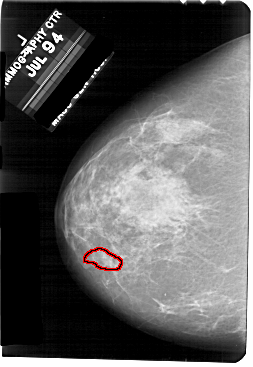

A_1707_1.LEFT_CC

LEFT_CC LINES 5491 PIXELS_PER_LINE 3781 BITS_PER_PIXEL 12 RESOLUTION 43.5 OVERLAY

FILE: A_1707_1.LEFT_CC.OVERLAY

TOTAL_ABNORMALITIES 1

ABNORMALITY 1

LESION_TYPE CALCIFICATION TYPE PLEOMORPHIC DISTRIBUTION CLUSTERED

ASSESSMENT 4

SUBTLETY 1

PATHOLOGY BENIGN

TOTAL_OUTLINES 1

BOUNDARY